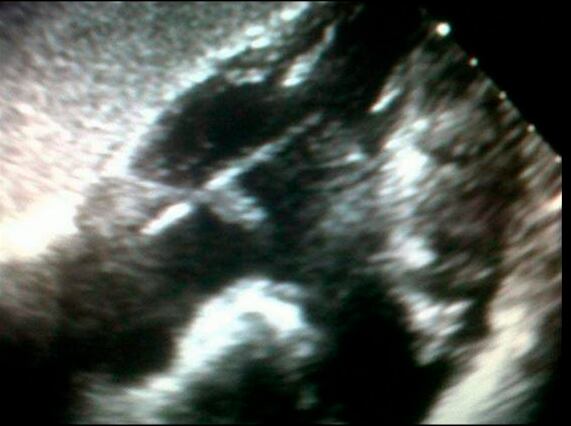

El paciente era Horacio Rodríguez Videla, un correntino radicado en la Ciudad de Buenos Aires, dueño de una empresa de fumigaciones. El hombre, por entonces de 43 años, llevaba siete meses con síntomas que nadie lograba explicar: fiebre alta, hipotermia y descenso de peso. Le habían hecho un sinfín de estudios para descartar desde una tuberculosis hasta un cáncer. Nada. En las imágenes solo se veía “como una flecha que se movía” dentro del corazón. La sospecha era que se trataba de un catéter que se había quedado allí tras alguna otra intervención.

A eso se sumaba un obstáculo clave: la madera no se ve ni en las radiografías ni en las tomografías. “Los rayos X atraviesan el material. Al principio veíamos una especie de ‘casquete’ —en medicina se llama granuloma— que aisló el elemento que le estaba produciendo la fiebre. Después esa imagen cambió radicalmente: veíamos una cosa larga y por eso pensamos que podía ser un catéter”, explica.